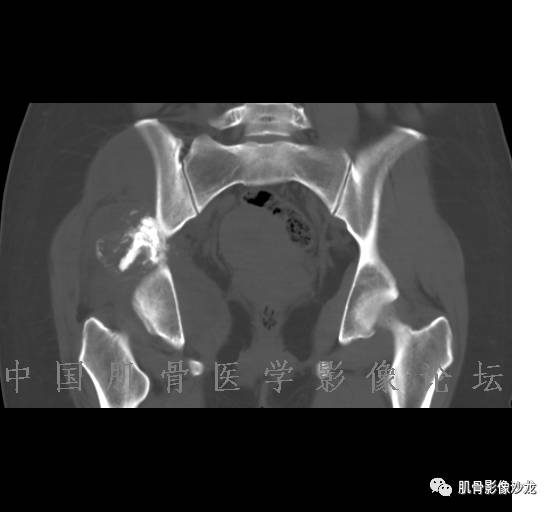

患者2月前无明显诱因下感右腿疼痛、麻木,疼痛呈持续性,发作时无法行走,休息后可缓解。当时无明显肿块,患者遂至当地医院就诊,查X片见右髂骨骨质破坏。6周前患者自觉右髋部渐大肿块,初肿块较小,后肿块逐渐增大,现肿块约12*10cm大小,有压痛。患者遂至我院就诊,查MRI:右髂骨异常信号,伴软组织肿块。ECT、肺CT未见转移。现患者为求进一步治疗,门诊拟“右髂骨肿块 ”收治入院。 患者发病来,神清,精神可,胃纳夜眠可,二便无殊,体重无明显变化。

信号 飞鹰行动:的确应该考虑软骨类肿瘤

飞鹰行动 : 软骨肉瘤内也有纤维组织的

飞鹰行动 : 第一列可以看见T2小结节样高信号,周围有纤维组织环绕

高回青 : 另外还可以见到扇贝状分叶

1、软骨肉瘤可以有膨胀性骨质破坏(病例3,4),可以有溶骨性骨质破坏(病例2),局部皮质因为破坏变薄,中断 ;

2、软骨基质T2WI高信号,软骨小叶分叶状,也就会出现高老师提到的骨内膜扇贝形压迹。一般认为骨内膜扇贝形压迹超过骨皮质厚度的2/3是软骨肉瘤在长管状骨的特征性表现。如上图。3、软组织肿块或肿胀;